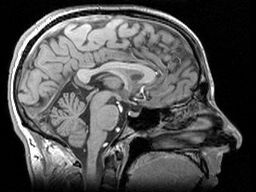

这些“变化”是什么?TRACK-HD 研究正在对每位受试者进行大量测量。磁共振成像 (MRI) 能够捕捉每位受试者大脑的详细三维图像。运动症状正通过多种方式进行测量,包括高科技眼动追踪和其他精密工具。许多测试旨在评估受试者的智力(或“认知”)功能及其情绪健康状况。最后,医生们还使用了多种评分量表来评估亨廷顿病 (HD) 的体征,这些也得到了测量,从而使 TRACK-HD 的科学家能够将他们的数据与早期试验进行比较。这些测试数量众多,TRACK-HD 的参与者们为整个亨廷顿病社区做出的贡献值得祝贺。

有了每位受试者的基线数据,TRACK-HD 的科学家们可以观察第一年每项测量的变化。在进行的数十项测量中,脑部成像得出的数据最为敏感。分析数百张三维图像的变化很困难,因此 TRACK-HD 科学家使用了三种完全不同的技术来确保他们观察到的变化不是由技术问题引起的。他们从每种技术得到的答案都非常一致,这让我们相信他们测量的是大脑的真实变化。

携带亨廷顿病 (HD) 突变的人群,其全脑体积下降速度更快,尽管未携带 HD 突变的人群大脑体积在一年内也会萎缩。已知对 HD 非常敏感的大脑特定区域,即尾状核和壳核,在携带 HD 突变的人群中退化得更快。该研究还发现大脑白质的早期损失,这非常重要,因为它相当于大脑的“线路”。

图片来源:生命科学数据库